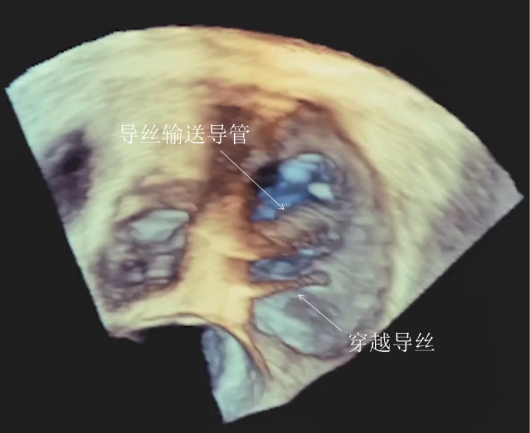

全麻下经右颈静脉入路,在食道超声及放射线引导下,将三尖瓣导丝输送导管经三尖瓣指引导管送至右心室,定位三尖瓣瓣环穿刺位点。穿越导丝连接高频发生器穿刺三尖瓣环(图2),在三尖瓣瓣环上植入一对锚片。通过缩短两个锚片之间的距离折叠三尖瓣瓣环,并通过3D-TEE、2D-TEE确认瓣环折叠及三尖瓣反流情况,最终实现三尖瓣瓣环的二瓣叶化(视频1),从而降低因瓣环扩大、瓣叶关闭不全产生的三尖瓣反流。

图2 :穿越导丝穿刺三尖瓣环(a:2D-TEE,b:3D-TEE)

视频1:a:锚片锚定三尖瓣瓣环,b:三尖瓣后瓣折叠